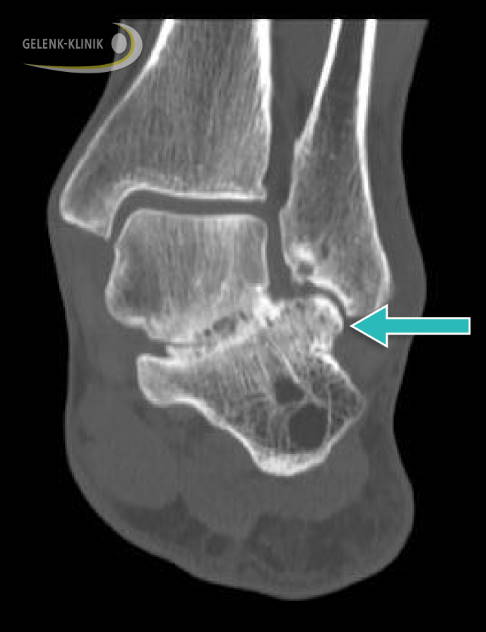

Fibulocalcaneares Impingement: Das Röntgenbild zeigt eine Einklemmung im oberen Sprunggelenk zwischen Wadenbein (Fibula) und Fersenbein (Calcaneus). © Gelenk-Klinik

Bei einem Impingement bilden sich je nach Ausmaß knöcherne Auswüchse am Schienbein und später auch am Sprungbein im vorderen Abschnitt des Sprunggelenks. An diesen Knochenvorsprüngen klemmen Weichteile wie die Gelenkschleimhaut oder Kapselanteile ein. Das Abrollen des oberen Sprunggelenkes (OSG) ist dann häufig schmerzhaft und die Beweglichkeit durch die Einklemmungen zunehmend eingeschränkt. Häufig leiden betroffene Sportler unter Sprunggelenkschmerzen beim Sport oder nach der Belastung. Die Freude am Sport wird hierdurch häufig zerstört.

Fibulocalcaneares Impingement: Bei dieser Form des Sprunggelenk-Impingements verspürt der Patient bei der Abrollbewegung des Fußes oder beim Gehen auf der Außenseite Beschwerden und heftige Schmerzen. Diese Schmerzen sind vor dem äußeren Sprunggelenk (Knöchel) oder unter dem Außenknöchel lokalisiert.